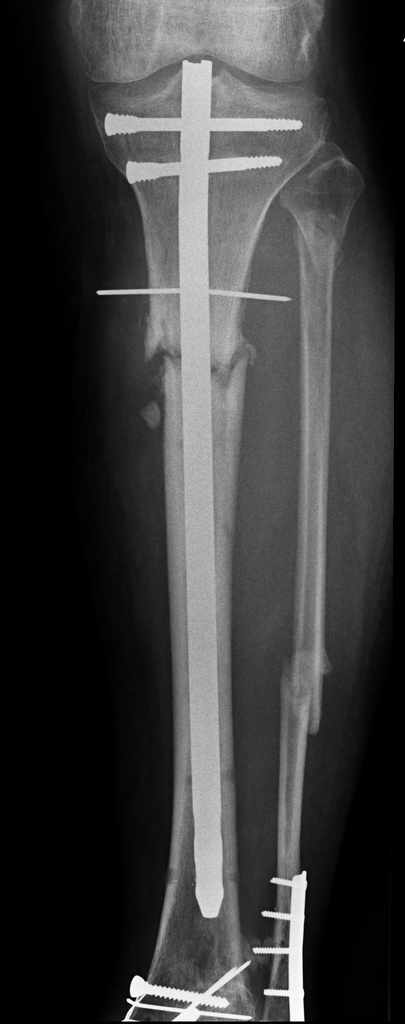

Открытый перелом- пхо+стержневой аппарат-штифтование. Через 4 месяца отек, температура 39….

Удален штифт-резекция+билокальный остеосинтез. Выращивание дистракционного регенерата

Повторное штифтование с рассверливанием. Оставлен дистально «легкий» аппарат для создания компрессии сближенных опилов на 4 недели.